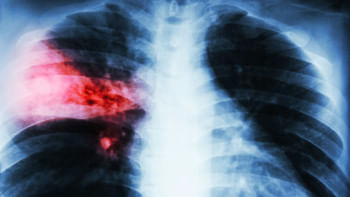

ডা. আব্দুস শাকুর খান বলেন, ফুসফুসের ক্যানসার হচ্ছে ফুসফুসের এক ধরনের টিউমার। অর্থাৎ ফুসফুসের যে স্বাভাবিক কোষ আছে সেই স্বাভাবিক কোষের যখন অস্বাভাবিক এবং অনিয়ন্ত্রিত বৃদ্ধি হয়ে চাকার মত সৃষ্টি করে, তাকেই ফুসফুস ক্যানসার বলে। এটি শরীরের জন্য মারাত্মক ক্ষতিকর। ক্যানসার যখন ফুসফুসে হয় এটা শুধু নির্দিষ্ট জায়গায় থাকে না বরং অস্বাভাবিক এবং অনিয়ন্ত্রিত বৃদ্ধির কারণে শরীরের অন্যান্য অংশেও ছড়িয়ে পড়ে। সঠিক সময়ে শনাক্ত ও যথাযথ চিকিৎসার অভাবে শেষ পর্যন্ত মৃত্যুরও কারণ হয়ে থাকে।

ফুসফুস ক্যানসারের অন্যতম লক্ষন হচ্ছে দীর্ঘমেয়াদী কাশি হওয়া, কখনো কখনো কাশির সঙ্গে কফ এবং কফের সঙ্গে রক্ত যাওয়া। ফুসফুসের ক্যানসারের কারণে বুকে ব্যথা হতে পারে। ক্যানসার যদি ব্যাপকতা পায় এবং বুকে পানি চলে আসে অথবা ফুসফুসে বেশি ছড়িয়ে পড়লে শ্বাসকষ্ট হতে পারে। এছাড়া কিছু সাধারণ লক্ষণ আছে, যেগুলো সব ক্যানসারেই দেখা যায়। যেমন- ওজন কমে যাওয়া, খাবারে অরুচি।